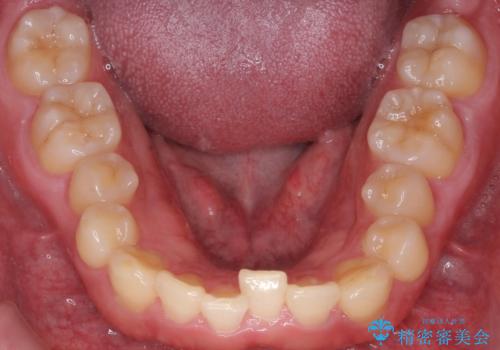

下の歯のがたつきが気になる。 インビザラン&ワイヤー部分矯正併用

- 下の歯が気になるとの事で来院。

左上の奥歯がシザーバイトがありワイヤーで部分的な矯正を行い、シザーバイトを改善した後にインビザラインで全体的な矯正治療を行いました。

歯のがたつきが改善され大変満足されました。